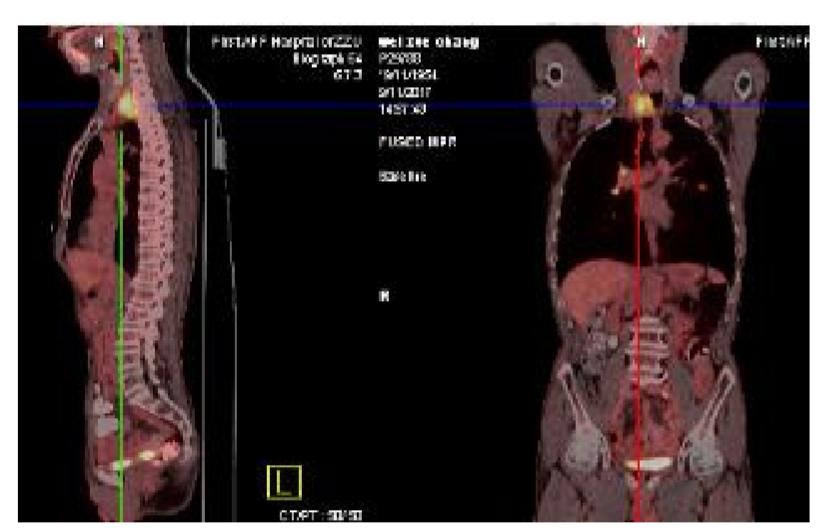

5.PET-CT(2017.09.11)

右侧颈部不规则软组织肿块代谢活跃,符合恶性病变,考虑食管来源伴周围淋巴结转移可能性大;双肺多发高密度结节代谢活跃,考虑转移。